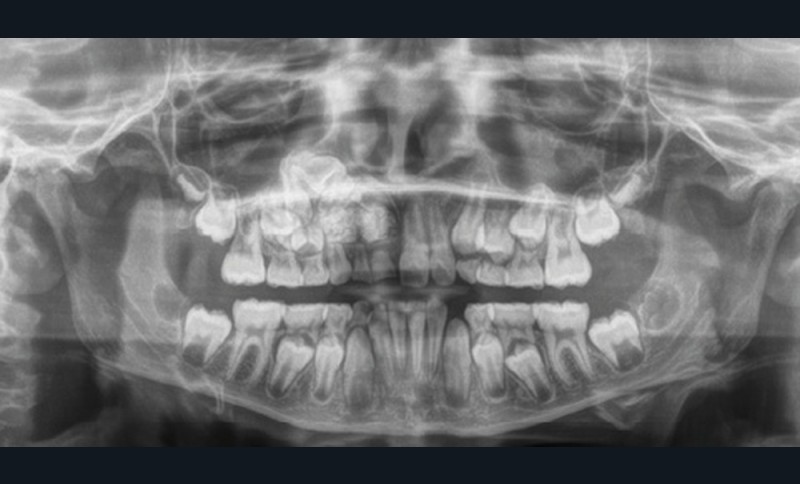

Les kystes et tumeurs bénignes osseuses maxillaires ou mandibulaires chez l’enfant sont le plus souvent asymptomatiques. Ces lésions osseuses sont découvertes de façon fortuite lors d’un bilan radiographique de routine réalisé par l’odontologiste pédiatrique ou l’orthodontiste [1-3]. Néanmoins, des lésions peuvent parfois se développer rapidement et être destructrices [1, 2]. Certains signes cliniques spécifiques à la chronologie de l’éruption dentaire chez l’enfant doivent nous alerter tels qu’un retard d’éruption dentaire ou une éruption dentaire asymétrique (fig. 1). D’autres manifestations cliniques, moins spécifiques à l’enfant, peuvent également orienter le clinicien sur la présence d’une pathologie osseuse sous-jacente : mobilité dentaire, douleur, tuméfaction, limitation de l’ouverture buccale, trouble neurosensoriel, etc. [3]. C’est la radiographie panoramique qui va ensuite mettre en évidence/confirmer la présence d’une lésion intra-osseuse (fig. 2).